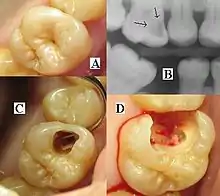

الشخص الذي يعاني من تسوس قد لا يكون على علم بالمرض.[11] أول علامة على وجود آفة نخرية جديدة تتمثل في ظهور بقعة بيضاء طباشيري على سطح السن، مما يشير إلى وجود منطقة تنزع عن المينا. يشار إلى هذا باسم آفة بقعة بيضاء، أو آفة نخرية أولية أو "جاذبية دقيقة".[12] بينما تستمر الآفة في إزالة المعادن، يمكن أن تتحول إلى اللون البني ولكنها ستتحول في النهاية إلى تجويف ("تجويف"). قبل أن يتشكل التجويف، تكون العملية قابلة للانعكاس، ولكن بمجرد تشكيل التجويف، لا يمكن تجديد بنية الأسنان المفقودة. تشير الآفة التي تظهر بلون بني غامق ولامع إلى أن تسوس الأسنان كان موجودًا في السابق ولكن عملية إزالة المعادن قد توقفت، تاركة وصمة عار. الاضمحلال النشط أخف في اللون ومظهره باهت.[13]

عندما يتم تدمير المينا والعاج، يصبح التجويف أكثر وضوحًا. المناطق المتضررة من الأسنان تغير لونها وتصبح ناعمة الملمس. بمجرد مرور التسوس من خلال المينا، تصبح الأنابيب الأنبوبية، التي لها ممرات إلى العصب السني، مكشوفة، مما ينتج عنه ألم يمكن أن يكون عابرًا، ويزيد سوءًا مؤقتًا مع التعرض للحرارة أو البرودة أو الأطعمة والمشروبات الحلوة.[14] يمكن أن تنهار فجأة في بعض الأحيان الأسنان التي أضعفتها التحلل الداخلي الواسع تحت قوى المضغ الطبيعية. عندما يتطور التسوس بشكل كافٍ للسماح للبكتيريا بتغلب أنسجة اللب في وسط السن، يمكن أن تحدث وجع الأسنان ويصبح الألم أكثر ثباتًا. موت أنسجة اللب والالتهابات هي عواقب شائعة. لن تكون السن حساسة بعد الآن للساخنة أو الباردة، لكنها قد تكون أكثر ضغوطًا.

عرض تسوس الأسنان متغير بدرجة كبيرة. ومع ذلك، فإن عوامل الخطر ومراحل التنمية متشابهة. في البداية، قد تظهر كمنطقة طباشيري صغيرة (تسوس الأسنان الملساء)، والتي قد تتطور في نهاية المطاف إلى تجويف كبير. في بعض الأحيان قد تكون تسوس مرئية مباشرة. ومع ذلك، يتم استخدام طرق أخرى للكشف مثل الأشعة السينية للمناطق الأقل وضوحًا في الأسنان وللحكم على مدى التدمير. يسمح الليزر للكشف عن تسوس الأسنان بالكشف دون أي إشعاعات مؤينة ويستخدم الآن للكشف عن التحلل المتداخل (بين الأسنان). تستخدم حلول الكشف أيضًا أثناء ترميم الأسنان لتقليل فرصة التكرار. [بحاجة لمصدر]

يتضمن التشخيص الأولي فحص جميع أسطح الأسنان المرئية باستخدام مصدر إضاءة جيد ومرآة أسنان ومستكشف. قد تُظهر صور الأشعة السينية (الأسنان بالأشعة السينية ) تسوس الأسنان قبل ظهورها بطريقة أخرى، وخاصة تسوس الأسنان. غالبًا ما تكون المساحات الكبيرة من تسوس الأسنان واضحة للعين المجردة، ولكن يصعب تحديد الآفات الأصغر. يتم استخدام الفحص البصري واللمسي إلى جانب الصور الشعاعية بشكل متكرر بين أطباء الأسنان، لا سيما لتشخيص تسوس الحفرة والتشقق.[86] غالبًا ما يتم تشخيص تسوس الأسنان المبكّر غير المموَّه عن طريق نفخ الهواء عبر السطح المشتبه فيه، مما يزيل الرطوبة ويغير الخصائص البصرية للمينا غير المعدنية.